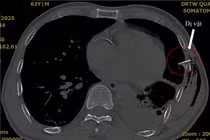

Bệnh nhân có vết thương kích thước khoảng 1x2 cm, bờ vết thương nham nhở, đáy lóc rộng, rách cơ ức đòn chũm và có dị vật cứng nhỏ, máu chảy rỉ rả.